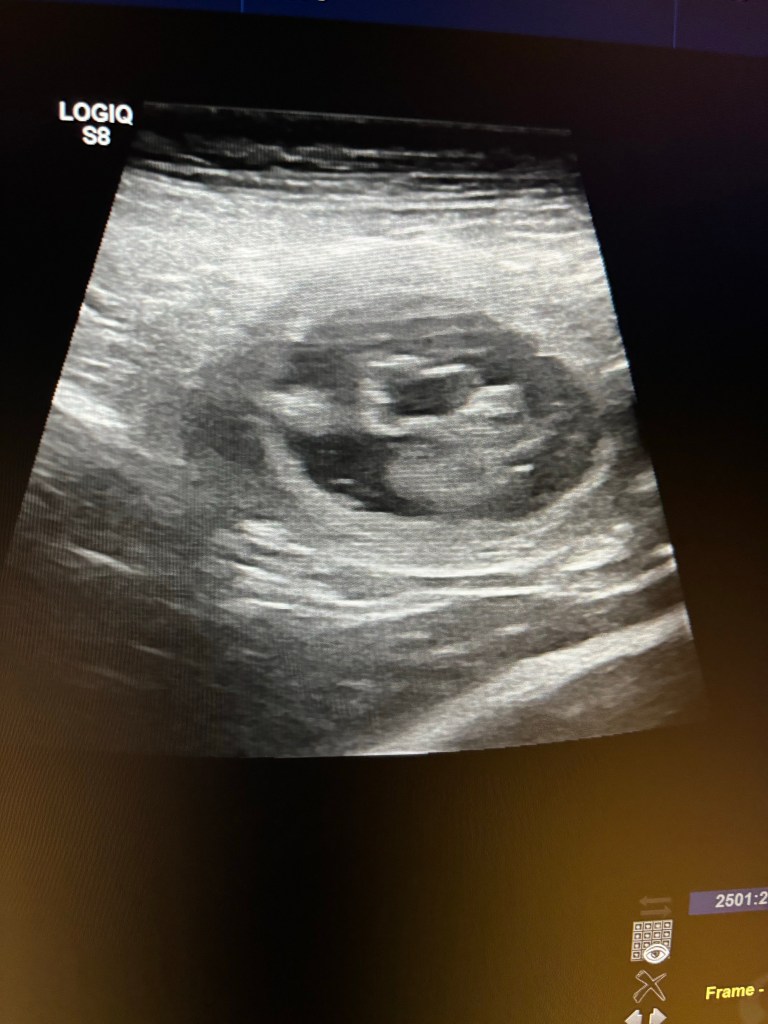

Vi väntar valpar v 4😍